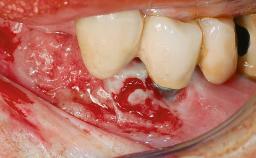

A 35-year old female patient was referred to the Department of Oral Surgery and Stomatology at the University of Bern, Switzerland, for examination of an implant site that had exhibited clinical signs of slightly delayed wound healing. In addition, the referring clinician found no evidence for a facial bone wall when she raised a flap to gain access to the implant for abutment connection. Four months earlier, she had inserted a bone-level implant in a single-tooth gap, where the lateral incisor had been extracted due to a chronic periapical lesion on the mesial aspect of the root. Implant placement was combined with simultaneous bone augmentation using deproteinized bovine bone mineral (DBBM, Bio-Oss®; Geistlich, Wolhusen, Switzerland) and a collagen membrane (Bio- Gide®; Geistlich), followed by primary wound closure. The patient also provided the postsurgical radiograph that displayed the implant with a 3.5-mm healing cap.

Bone Volume Deficient horizontally, allowing simultaneous augumentation